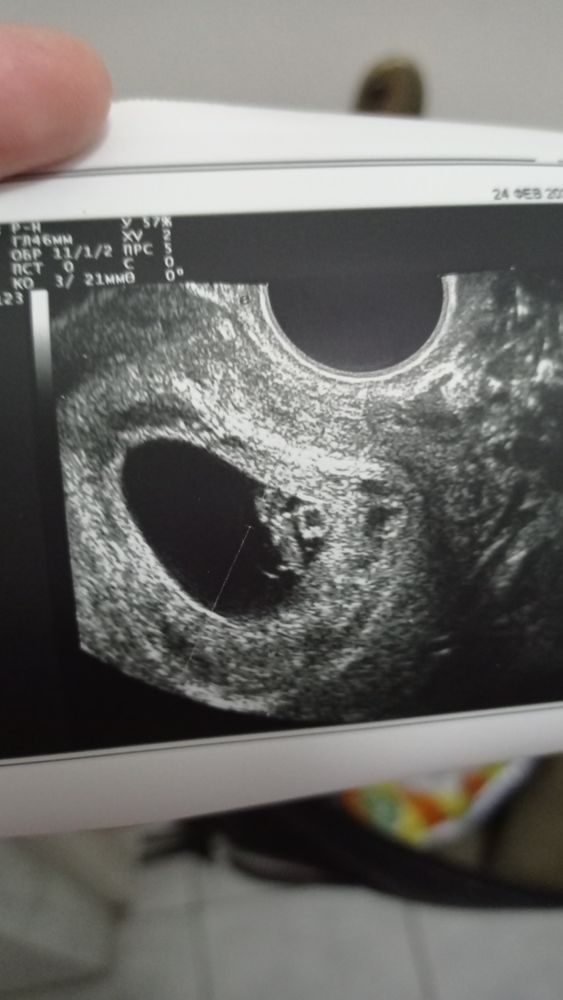

Первое УЗИ😍

И сразу попала на УЗИ

Теперь можно и на учет вставать)

Сердечко уже слышно

Срок чуть больше, чем по М